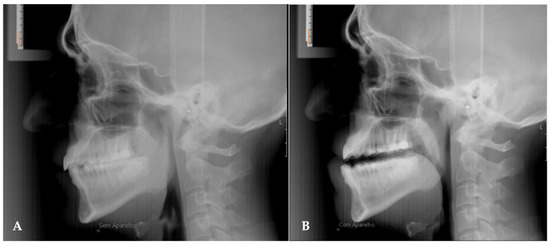

The linear measurements of the airspace proposed by the Arnett/Gunson FAB Surgery cephalometric analysis were measured at four craniometric points: A, MCI, B, Pog (Figure 3):

• SPAS at point A (SPAS at A): A line is drawn perpendicular to the true vertical line that passes through point A and extends posteriorly, intersecting the anterior (A/G anterior SPAS at A) and posterior (A/G posterior SPAS at A) limits of the superior posterior airway space. The dimension of the UA is given by the distance between these two points.

• SPAS at point MCI (SPAS at MCI): A line is drawn perpendicular to the true vertical line that passes through point MCI (point located on the incisal edge of the maxillary central incisor) and extends posteriorly, intersecting the anterior (A/G anterior SPAS at MCI) and posterior (A/G posterior SPAS at MCI) limits of the superior posterior airway (Figure 3—Points 8 and 9).

• SPAS at point B (SPAS at B): A line is drawn perpendicular to the true vertical line that passes through point B and extends posteriorly, intersecting the anterior (A/G anterior SPAS at B) and posterior (A/G posterior SPAS at B) limits of the superior posterior airway space.

• SPAS at point Pog (SPAS at Pog): A line is drawn perpendicular to the true vertical line that passes through point Pog at the anterior (A/G anterior SPAS at Pog) and posterior (A/G posterior SPAS at Pog) wall of the superior posterior airway.

Figure 3. Cephalometric points: (1) A-point, (2) MCI-point, (3) B-point, (4) Pog-point, (5) A/G tip of soft Palate, (6) A/G anterior SPAS at A, (7) A/G posterior SPAS at A, (8) A/G anterior SPAS at MCI, (9) A/G posterior SPAS at MCI, (10) A/G anterior SPAS at B, (11) A/G posterior SPAS at B, (12) A/G anterior SPAS at Pog, (13) A/G posterior SPAS at Pog.